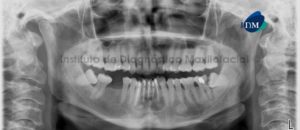

Paciente femenino de 62 años de edad acude al Instituto de Diagnostico Maxilofacial para evaluación general debido a que se le realizará una rehabilitación oral